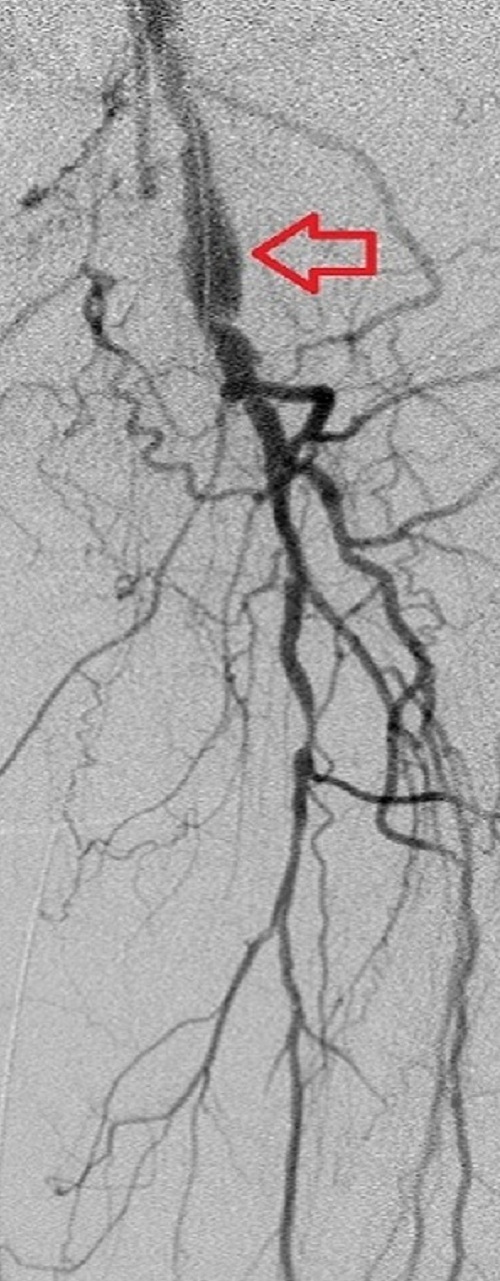

Key to images:

Top panel: Pre-intervention run-off angiogram of the left lower extremity showing, from left to right, irregular left common femoral artery (LCFA) arrowed on the 1st image, absent left superfical femoral artery (LSFA) or any bypass conduit on the 2nd image, sketchy descending collaterals from the left deep femoral (LDFA) that reconstitute a faint shadow of the left popliteal artery, arrowed on the 3rd image. The last 2 images faintly show three-vessel run-off below the left knee. The anterior tibial artery is most opacified, followed by the posterior tibial artery; the peroneal artery peeps through the upper edge of the last image. Note how weakly visible these vessels are due to the poor inflow from above.